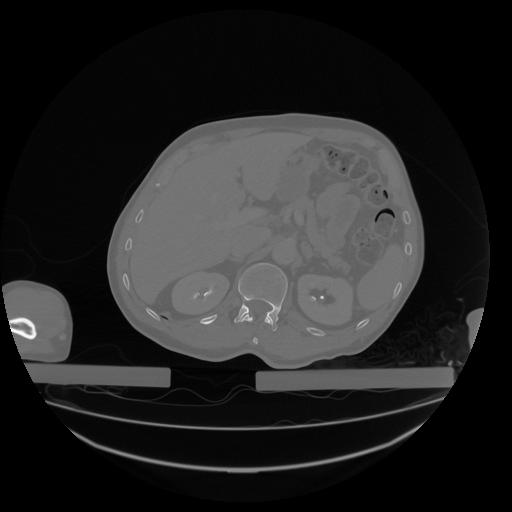

34 CUERPO,CE,Vol,1.0,CUERPO,,